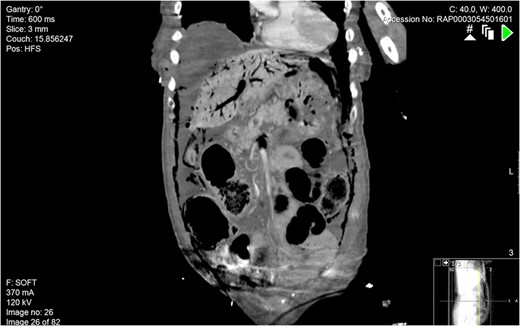

Subsequently a computerized tomography scan was performed of her chest, abdomen and pelvis (CTCAP), showing hepatic portal venous gas (HPVG), with visible air fluid levels (Fig. 1). There was a large amount of free air and free fluid within the abdomen and pelvis, highly suspicious for perforation (Fig. 2). There was also partial ischaemia of liver segment seven.

Coronal section of abdominal CT scan. A large amount of gas can be seen within the hepatic portal venous system.